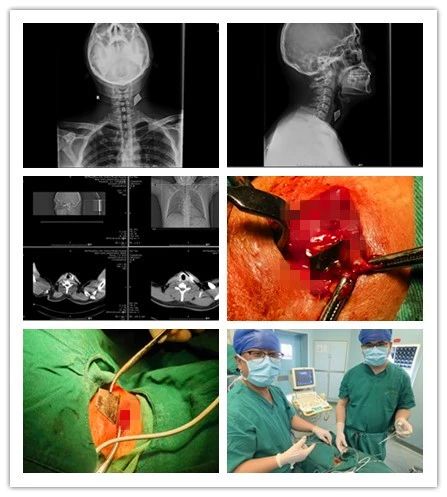

近日,一位“美工刀”刀刺傷的患者來我院乳腺甲狀腺外科就診,頸部正側位拍片顯示“美工刀片”深入頸深部,嚴重危及生命。乳腺甲狀腺外科團隊以十分鐘的“小手術”成功為患者解除危機,患者現已痊愈出院。

患者,男,35歲,3個月前頸部被銳器刺傷,傷后出血量約50ml,伴有疼痛,不伴有麻木,呼吸正常,于外院行清創縫合手術,術后切口反復感染,并伴有頸部及左側上肢放射性疼痛,后于我院復查頸部正側位片示左側頸前不規則致密影,門診以“左頸部異物”收入院。

乳腺甲狀腺外科王思雷和楊汶士主治醫師接診后,追問患者病史并仔細檢查,確認患者皮膚淺層不存在異物,認為異物存在于頸深部,且異物為銳器“美工刀片”,有傷及頸部大血管及氣管、食管可能,隨時危機生命,建議手術取出。但異物位置深,緊鄰頸部大血管、氣管、食管,存在較大手術難度和風險。科主任李峰和王思雷、楊汶士主治醫師進行充分術前討論后,制定了周密的手術方案,在彩超及C臂機引導下,精確定位,為患者施行頸部異物取出術+清創縫合術。術中發現異物為銳器“美工刀片”,刀刃鋒利,位置深達頸椎前側,緊鄰頸部大血管及氣管、食管,差之毫厘便可能造成血管破裂致大出血。兩位醫師憑借嫻熟的技術,小心翼翼探查,僅用十分鐘便成功取出異物。